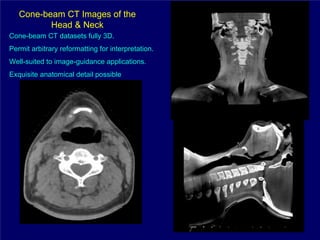

Cone-beam CT Images of the

Head & Neck

Cone-beam CT datasets fully 3D.

Permit arbitrary reformatting for interpretation.

Well-suited to image-guidance applications.

Exquisite anatomical detail possible